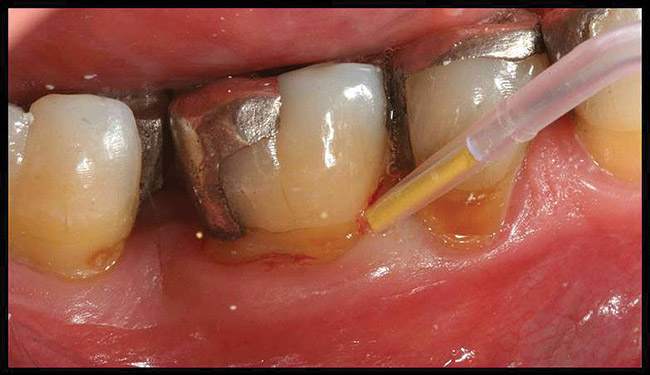

Inflammation limited to soft tissues around a dental implant may result from dental plaque colonization and is termed peri-implant mucositis. This is a reversible inflammatory condition limited to the soft tissues around the implant (without any bone loss), analogous to gingivitis around natural teeth. A diagnosis of peri-implantitis results when the inflammation spreads apically, causing progressive loss of osseointegrated supporting bone, analogous to periodontitis around natural teeth16 (Figure 2A and Figure 2B). It is essential for practitioners to be familiar with these diagnostic terms when assessing the long-term success of implants and peri-implant health (Table 1).

Figure 2a

Figureb 2  (A) Clinical and (B) radiographic views of implants at site Nos. 30 and 31 demonstrating bone loss caused by peri-implantitis after 8 years in function. Note gingival inflammation and plaque accumulation around implants.

Figure 2b